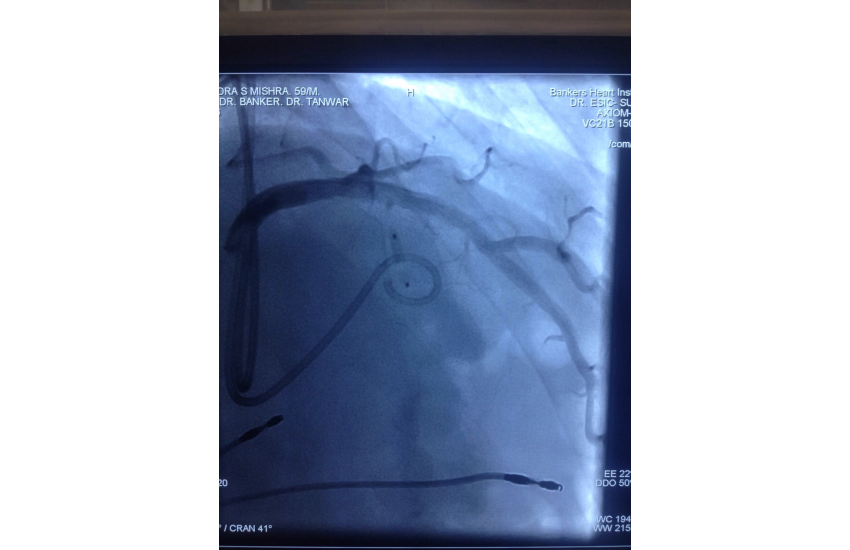

Twiddlers Syndrome

14 Jun 2006